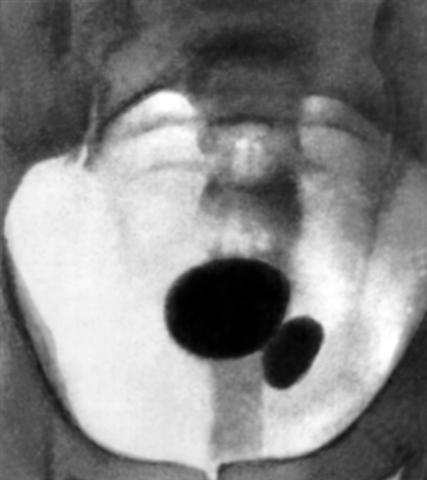

Рис. 2а). Цистограмма больных аденомой предстательной железы: характерный овальный дефект наполнения, соответствующий аденоме предстательной железы.